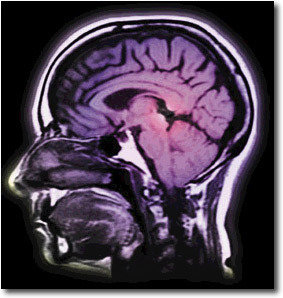

La ingesta de bebidas alcohólicas provoca la secreción de las endorfinas en determinadas zonas del cerebro y esto hace que se produzca sensación de placer, lo cual podría conducir a la adicción de esta.

Estas proteínas tienen efectos opiáceos y se liberan en el núcleo accumbens y en la corteza orbitofrontal, que se encuentran en el cerebro, no obstante se ha descubierto que el receptor opioide que actúa con ellas es el receptor Mu, por lo que este descubrimiento permitirá mejorar los métodos y medicaciones para tratar los problemas con el alcohol.